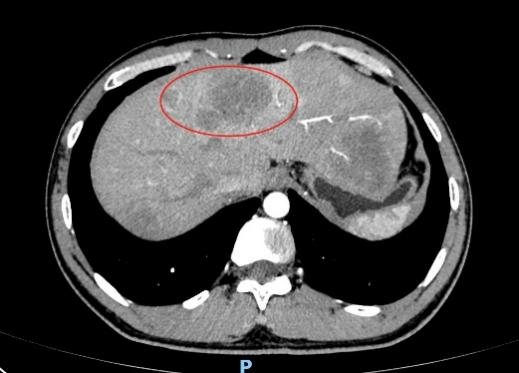

随后的病理结果提示,小秦确诊结直肠多发息肉病,其中多枚较大息肉已经进展为腺癌,且CT显示肝脏有异常结节,考虑癌细胞转移,已经到了晚期,仅切除肠道病变对生存意义不大。目前小秦在我院肿瘤科进行化疗,希望能将肿瘤缩小转化,创造手术机会。医护对此都感到很痛心。

(CT下显示肝脏转移)